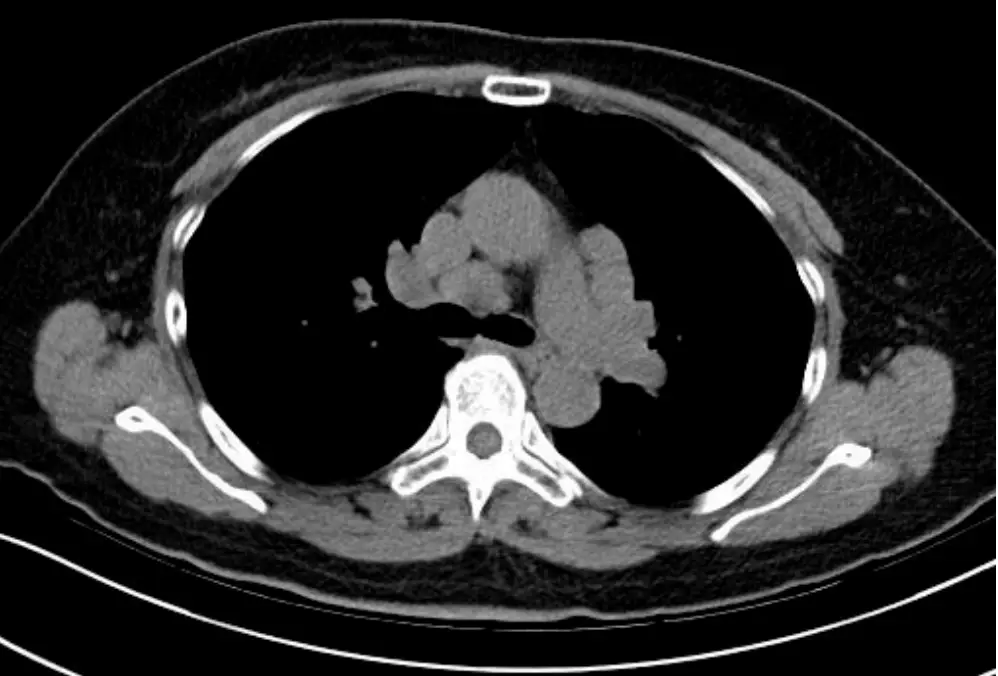

- CT橫截面影像(上段、中央):

- 在肺門及縱隔區域,淋巴結明顯腫大,形態規則、邊界完整、密度均質,無中央壞死或環形增強。

- 肺實質可見多發性微小結節,沿支氣管血管束分佈(peribronchovascular distribution),並可見部分結節沿間質(interlobular septa)與胸膜下區域延伸,呈現「經淋巴路徑分佈」(perilymphatic)特徵。

- 無單一實質腫塊、無大範圍實變或空洞。

上述對稱性雙側肺門與右側縱隔淋巴結腫大,合併肺野小結節沿支氣管血管束與胸膜下區域呈節結狀,極符合Sarcoidosis的典型影像特徵。